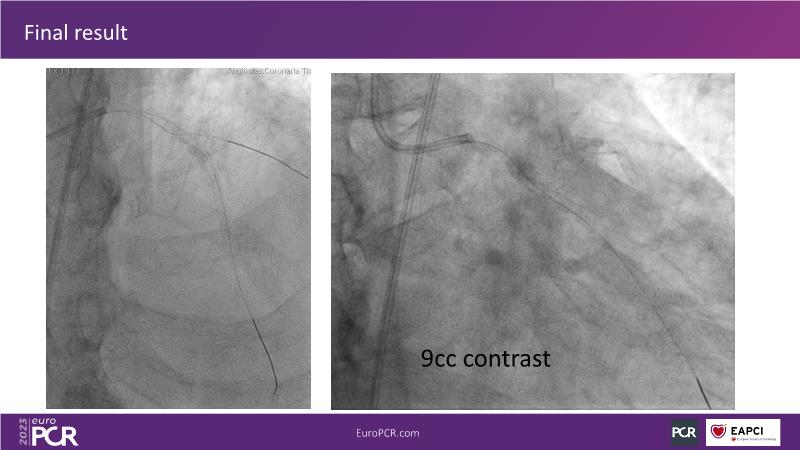

Discover the indispensable toolset of ultra-low contrast (ULC) percutaneous coronary intervention (PCI) in complex coronary interventions and higher-risk patients in this session. Gain a comprehensive understanding of how ULC PCI can enhance the safety and quality of revascularization in complex procedures and learn practical aspects from recorded cases, including specific approaches utilizing intracoronary imaging, physiology, and dedicated tools and techniques.

- To learn practical aspects from recorded ULC PCI cases, including specific approaches using intracoronary imaging, physiology and dedicated tools and techniques